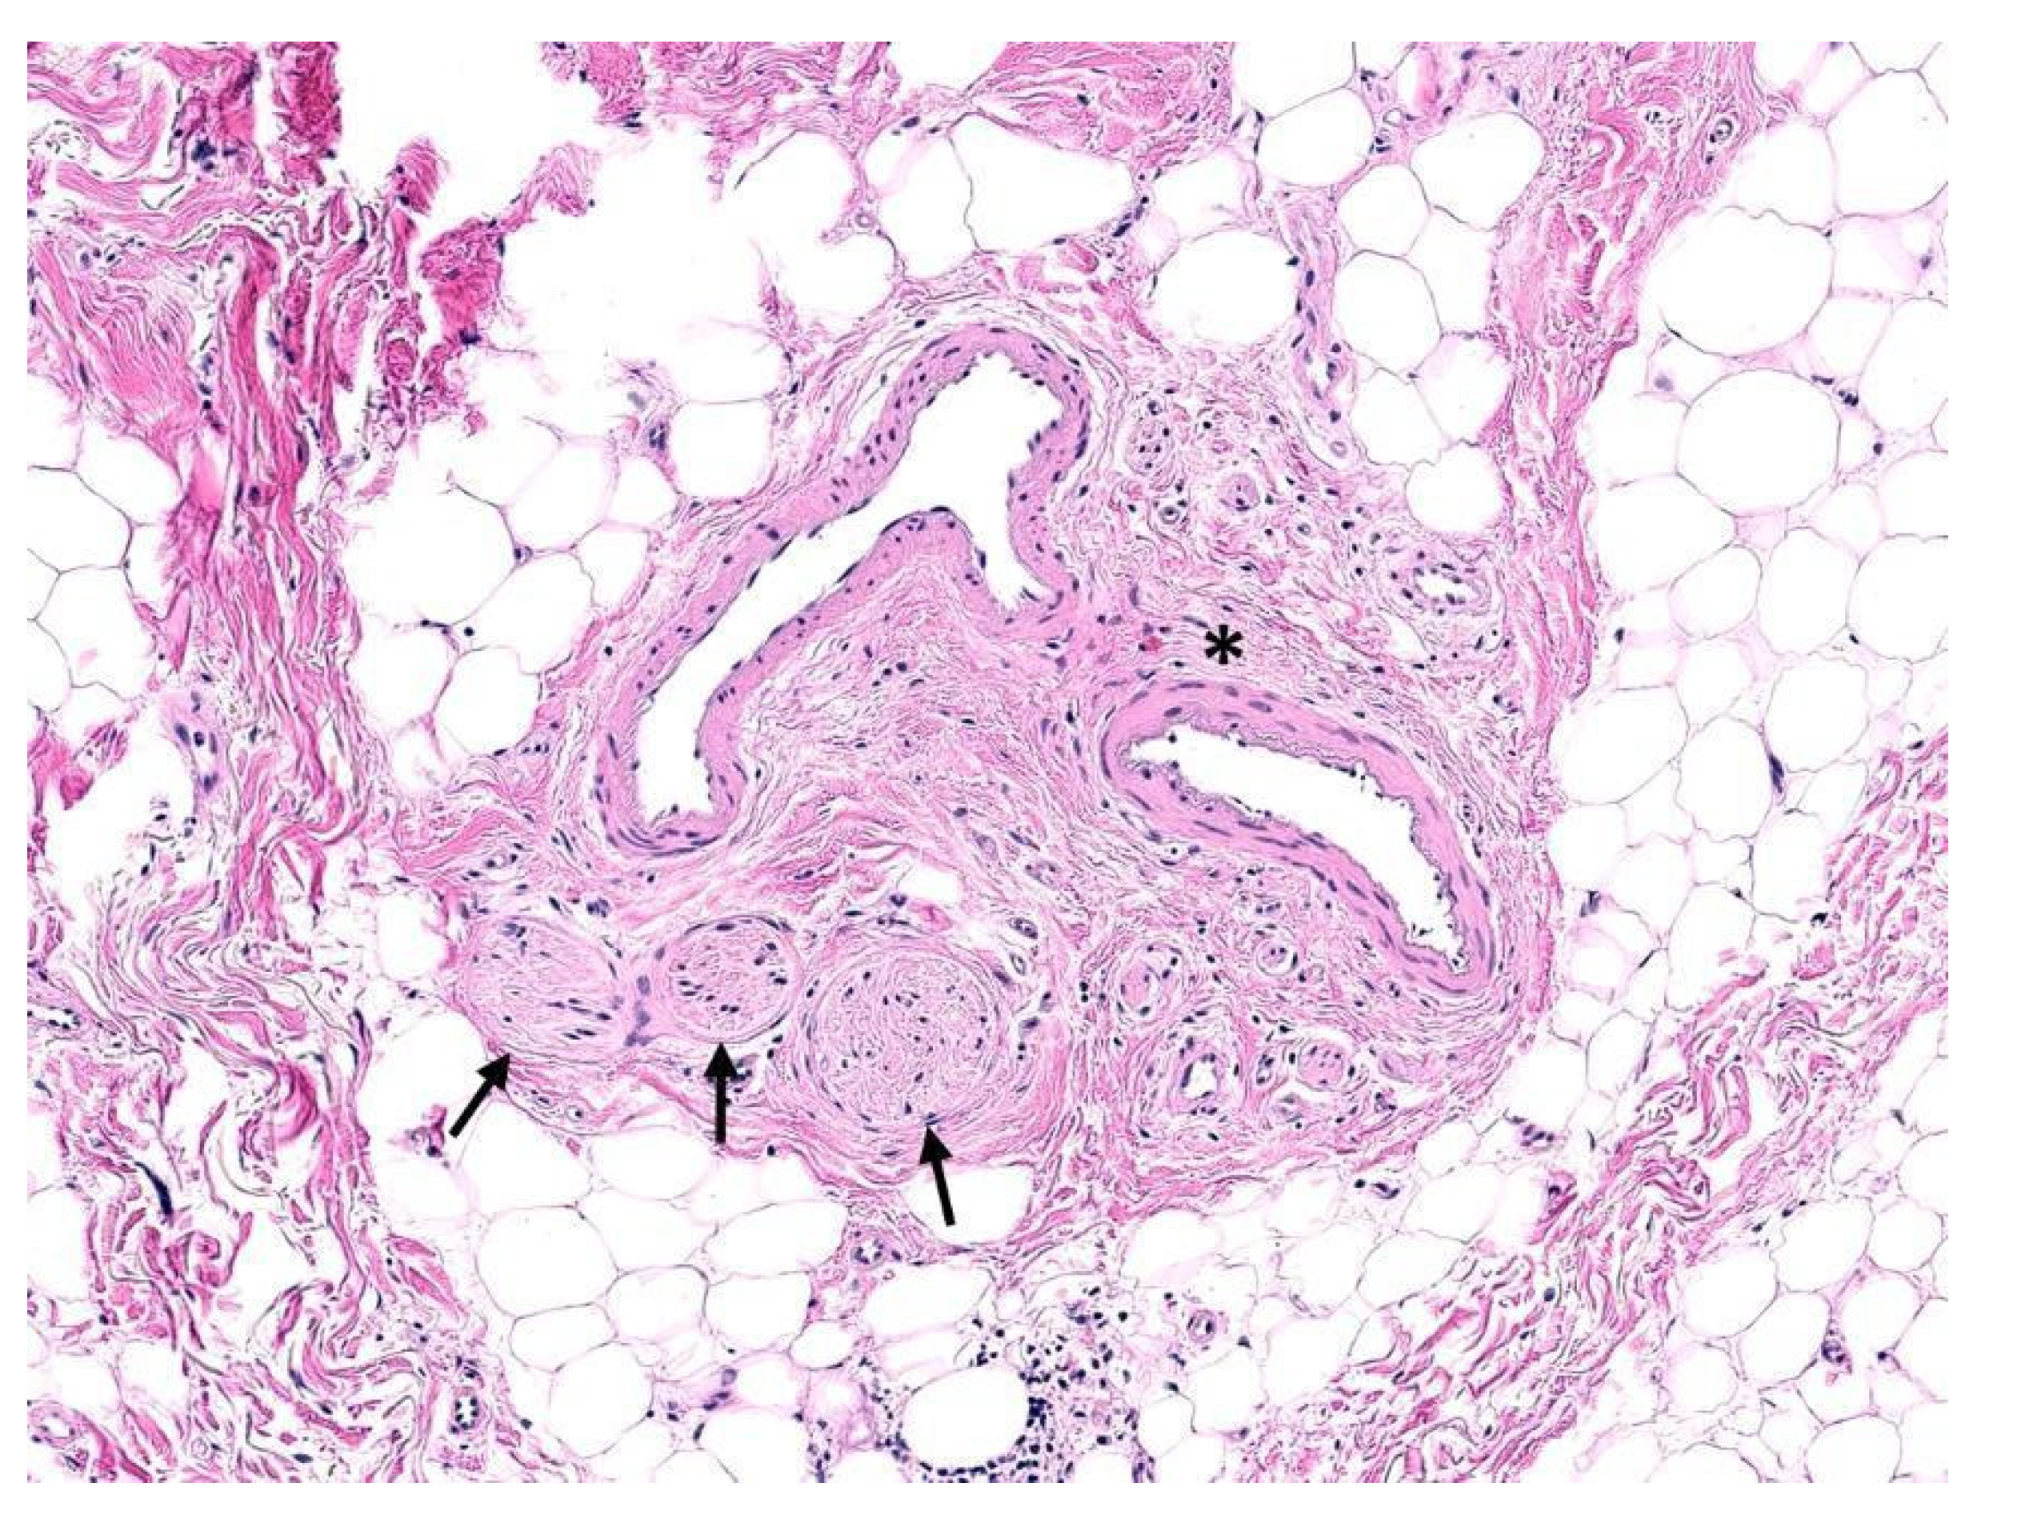

3. Perineurial Invasion

Abstract